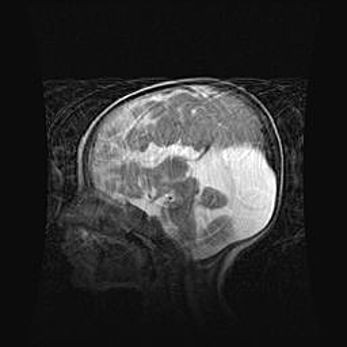

Сообщающаяся гидроцефалия. Кистозная энцефаломаляция головного мозга.

Возраст: 3 месяца 4 дня

Вес: 3100 г

Пол: женский

Окружность головы: 34 см

Срок гестации: 31 неделя

Кистозная энцефаломаляция головного мозга - одна из форм поражения головного мозга в детском возрасте. Характеризуется возникновением множественных и распространённых кист в коре, белом веществе и подкорковых образованиях головного мозга у плодов, новорождённых и детей раннего возраста. Развитие кистозной энцефаломаляции связано с внутриутробной асфиксией и гипотонией, родовой травмой, тромбозом синусов, пороками развития сосудов, инфекциями, сепсисом и другими причинами. Наиболее значимые инфекционные агенты: вирусы простого герпеса, цитомегалии, краснухи, токсоплазмы, энтеробактерии, золотистый стафилококк и другие.